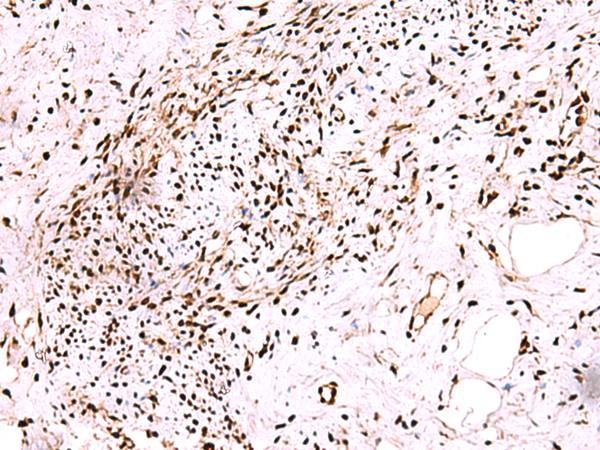

分类: 科研抗体货号: P00259别名: P21; CIP1; SDI1; WAF1; CAP20; CDKN1; MDA-6; p21CIP1应用: WB,IHC反应种属: Human